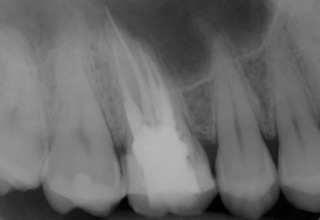

Nach Darstellung aller Wurzelkanaleingänge wird in einem zweiten Schritt das frakturierte Wurzelkanalinstrument dargestellt (Abb. 3 u. 4). Hierfür verwenden wir den Aufsatz 3E des Tigon+. Durch die schmale und lange Form des Instruments erreichen wir einen tiefen und schmalen Zugang.